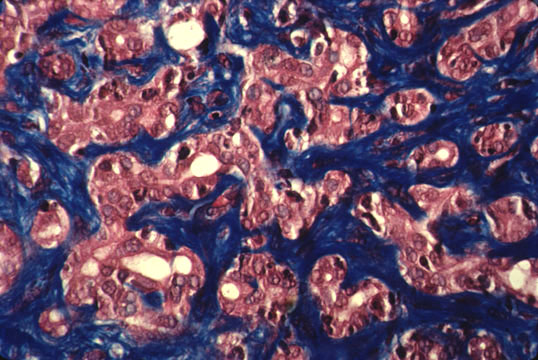

BILIARY FIBROSIS

It is characterized by portal fibrosis with marked ductular proliferation extending to porto-portal septa and transformation of the liver parenchyma into sharp "garland" shaped nodules. It should not be confused with cirrhosis since this type of biliary fibrosis that is due to a chronic biliary obstruction may be reversible. The plexiform ductular proliferation in portal fields and septa is the hallmark of this lesion.

Fig.72 - BILIARY FIBROSIS: Severe nodular transformation of the liver by porto-portal fibrosis septa without inflammatory cells in clean obstructive jaundice.